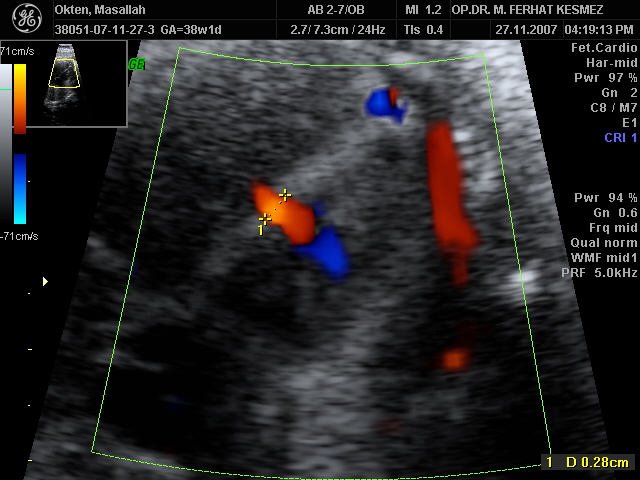

Ultrason Ölçümleri